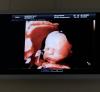

Копия старшего сына 😂😂

Интересно, когда родится, будет ли также сильно похож)

Посмотрела вашу страничку,реально копия😁 лёгких родов вам ☺️